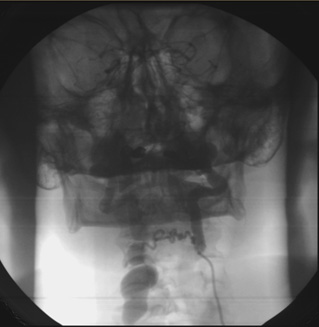

Проведено обследование: Рентгенография органов грудной клетки: в верхнем средостении над дугой аорты определяется массивное образование с неровными бугристыми контурами, значительно проступающее в правое легочное поле. На этом уровне отмечается девиация контрастированного пищевода влево и кпереди и S-образное сколиотическое искривление нижнешейного отдела позвоночника.

Ангиография брахиоцефальных артерий: восходящая аорта, дуга, нисходящая аорта без патологических изменений. Проксимальный сегмент правой позвоночной артерии извит, расширен. Визуализируется гигантское мешковидное образование размером 85×130 мм от уровня С5, занимающее всю область шеи, подчелюстную область и спускающееся в грудную полость по ходу верхней полой вены (рис.5). Отмечается сужение правой подключичной артерии до 80% при выходе из реберно-ключичного пространства. Правая общая сонная артерия — девиация в среднем отделе. Выполнена ангиография брахиоцефальных сосудов и селективная ангиография полости аневризмы. Верхняя граница аневризмы визуализируется до интракраниального отдела правой позвоночной артерии. При ангиографии левой позвоночной артерии выявлен переток в систему правой позвоночной артерии с контрастированием аневризмы (рис.6). Левые позвоночная, общая сонная артерия — без особенностей. Клинический диагноз: Гигантская аневризма правой позвоночной артерии. Миелопатия от длительного сдавления в шейном отделе позвоночника смешанного генеза (компрессионная, ишемическая). Дисциркуляторная энцефалопатия в вертебро-базилярном бассейне. Нейрофиброматоз I типа (синдром Реклингаузена). Медикаментозное лечение: детралекс, дексазон, эуфиллин, карнитин, мексидол. Учитывая, что полость аневризмы заполнялась как антеградно, так и ретроградно (через базилярную артерию), было решено первым этапом локализовать аневризматический мешок в дистальном отделе эмболизацией позвоночной артерии спиралями GIANTURCO (COOK) доступом через контрлатеральную позвоночную артерию. Однако, в связи с техническими трудностями прохождения проводника и катетера через базилярную артерию, решено воздержаться от выполнения данной процедуры и попытаться закрыть аневризму из антеградного доступа имплантацией устройства «Amplatzer» для закрытия открытого артериального протока в проксимальный отдел правой позвоночной артерии.

Рис.5 Ангиография аневризмы правой позвоночной артерии.